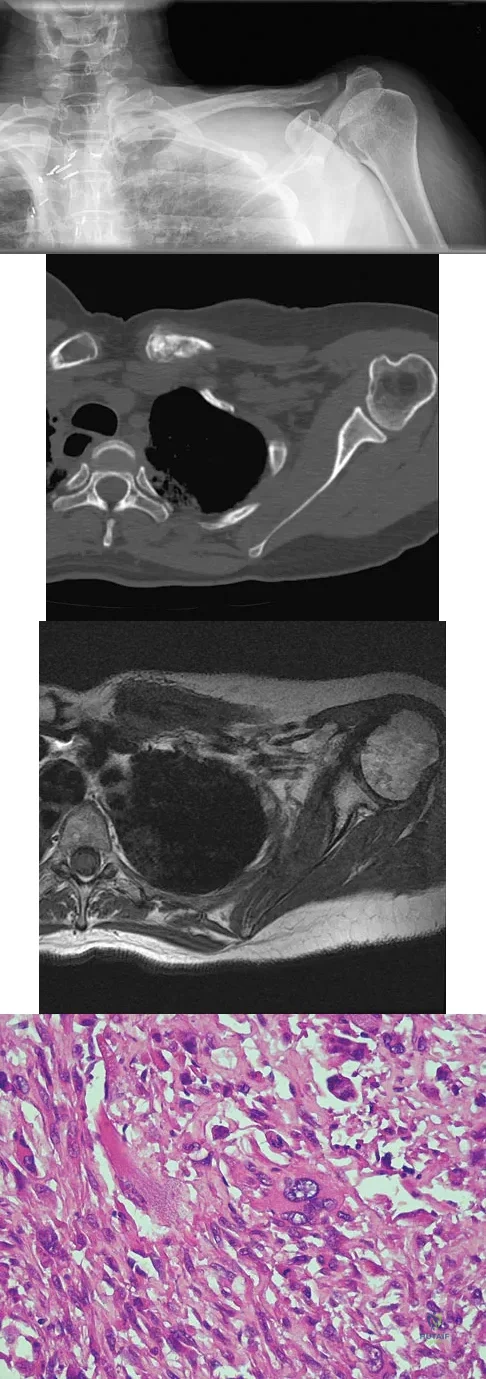

A 23-year-old man has had right posterolateral knee pain and occasional lateral calf dysesthesias for the past 8 months. A radiograph, CT scan, MRI scans, and a biopsy specimen are shown in Figures 62a through 62e. What is the most likely diagnosis?

A 47-year-old woman has had left medial clavicle pain for the past 6 months. History is remarkable for mediastinal non-Hodgkin's lymphoma, treated with mantel radiation 22 years ago. A radiograph, CT scan, MRI scan, and a biopsy specimen are shown in Figures 68a through 68d. What is the most likely diagnosis?

A 16-year-old girl has had hip pain for 1 year. Approximately 2 months ago she noted the development of a hard mass in the right buttock that has steadily increased in size. She now reports severe pain in the right buttock, with radiation down the leg and numbness involving the right foot and toes. A radiograph is shown in Figure 70a and an axial postcontrast T1-weighted MRI scan is shown in Figure 70b. A biopsy specimen is shown in Figure 70c. The chest CT shows multiple lung metastases. Treatment of this lesion should consist of